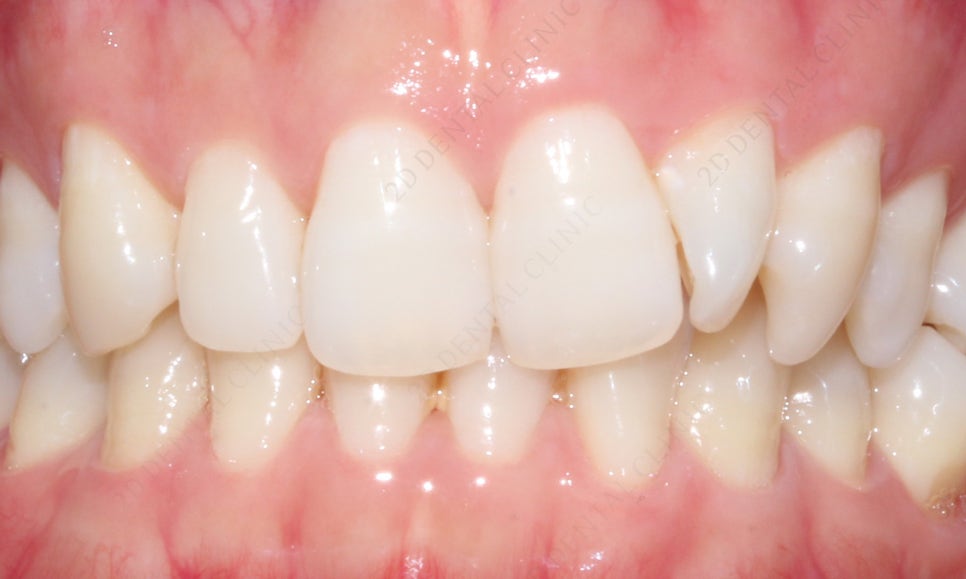

2D치과(투디치과) 앞니교정 기간 [4개월 소요]

회전이 되어있던 측절치가 제자리로

개선이 완료 되었어요.

환자분께서 신경이 쓰이셨던

덧니 같은 느낌의 치아도 사라지고 자신 있게

웃을 수 있다며 많이 좋아하셨답니다